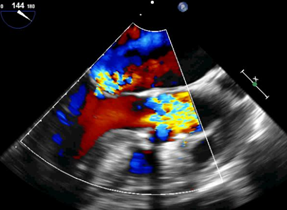

近日,华中科技大学同济医学院附属协和医院心脏大血管外科启动佰仁医疗Salus介入肺动脉瓣临床试验入组,并于当天成功完成1例经胸介入肺动脉瓣植入,获得了理想的治疗效果。

近日,四川大学华西医院心脏大血管外科安琪教授团队与心脏内科冯沅教授团队联合启动佰仁医疗Salus介入肺动脉瓣临床试验入组,并于当天成功完成1例经胸小切口介入肺动脉瓣植入,获得了理想的治疗效果。

2022年7月23日,武汉大学中南医院结构性心脏病中心张刚成、刘金平教授团队正式启动佰仁医疗Salus介入肺动脉瓣临床试验入组,并于当天与阜外华中心血管病医院范太兵教授团队合作成功完成1例经胸介入肺动脉瓣植入,该研究由首都医科大学附属北京安贞医院牵头,联合多家知名心脏中心参与,是国内首个经胸介入肺动脉瓣临床试验,具有重大意义。